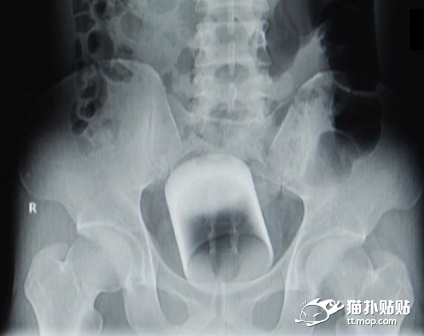

gif_animation オナニーの数倍気持ちいと言われる「肛門オナニー」をやり過ぎた男の末路。”抜けない” と病院を訪れた男のお尻からは、直径7cmのコップが摘出された。[5]img